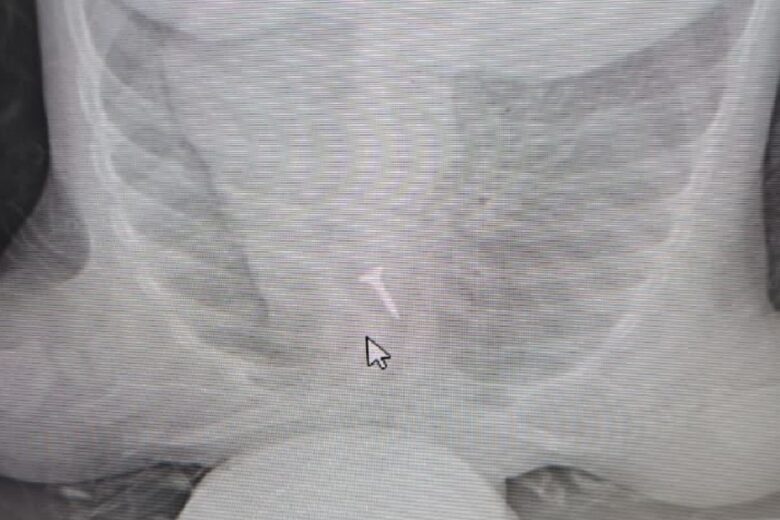

«В больницу Устюжны привезли малыша 10 месяцев: дома была рвота, одышка, ребенок побледнел. Врачи приняли, осмотрели пациента, вызвали рентгенолаборанта и сделали снимок легких. Ярким пятном на картинке сиял… саморез», - сообщает региональный Минздрав.